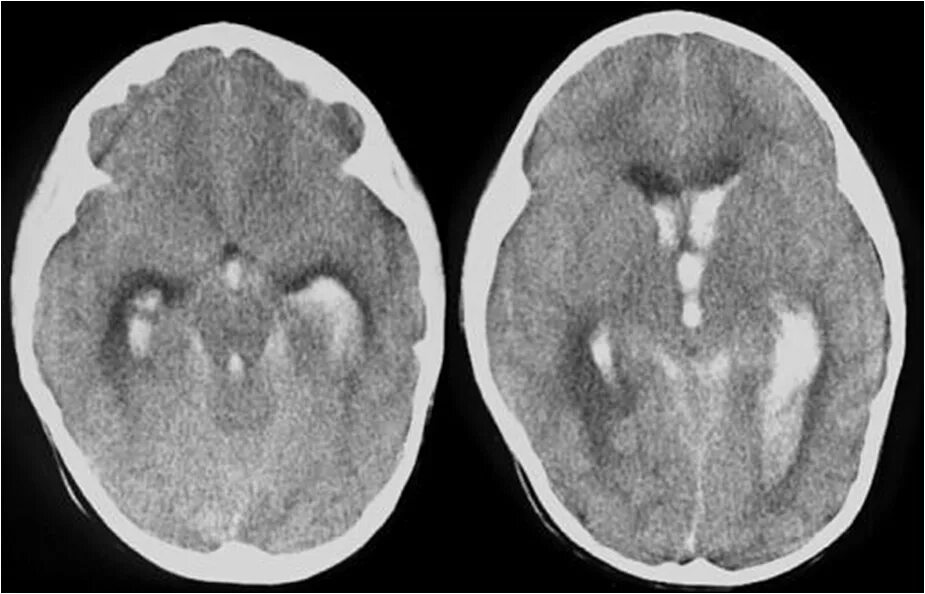

Внутрижелудочковое кровоизлияние